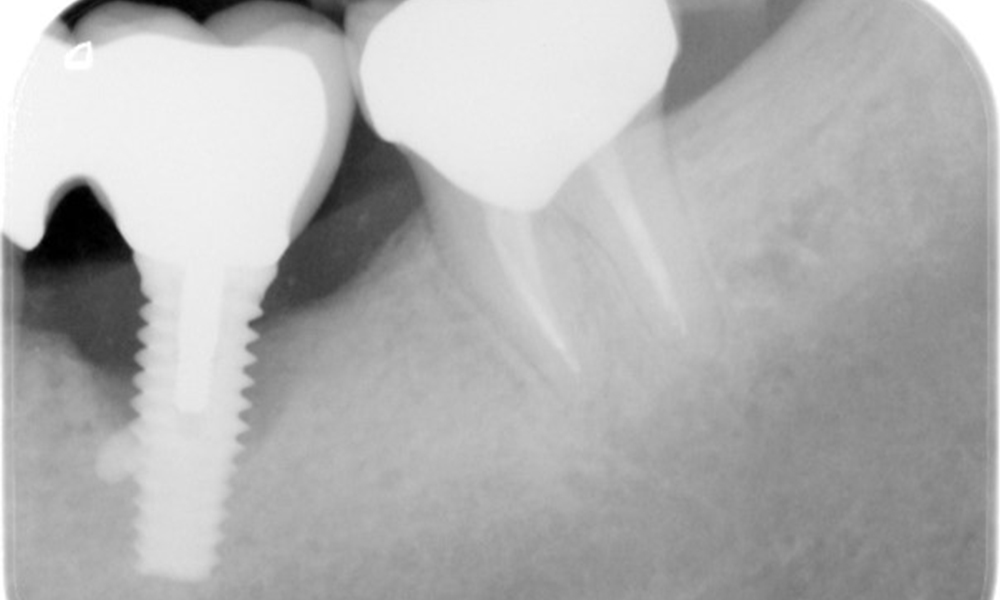

Der Patient zeigt keine besonderen anamnestischen Risikofaktoren mit spezifischen zahnmedizinischen Auswirkungen. Daher ist der aus der Mundgesundheit ermittelte Bedarf maßgebend. Hierbei zeigt sich am Implantat im 3. Quadranten ST von 5 mm und im Röntgenbild eine Zunahme des Knochenverlustes. Der Patient hat zudem eine aktuell stabile parodontale Vorerkrankung und zwei aktive initialkariöse Läsionen.